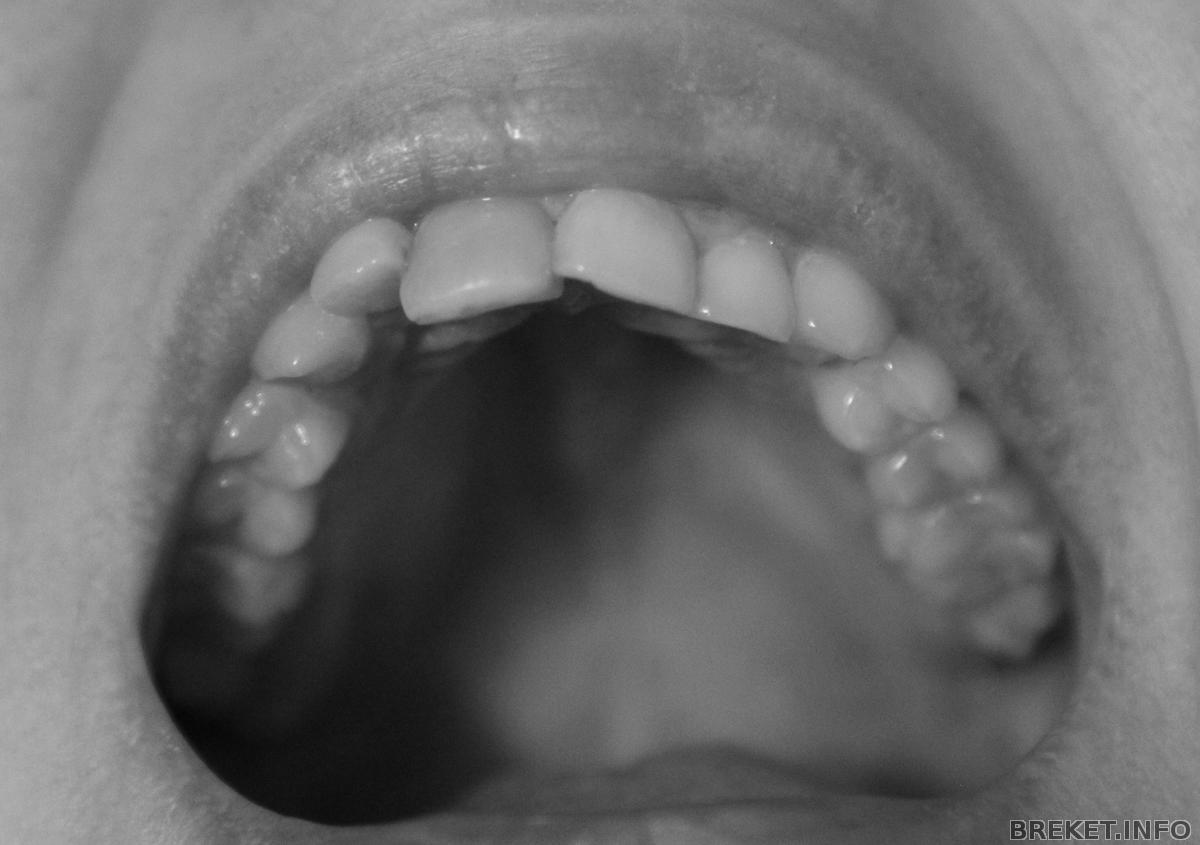

Вот, выношу на ваш суд свои зубки:

img_5351b.jpg